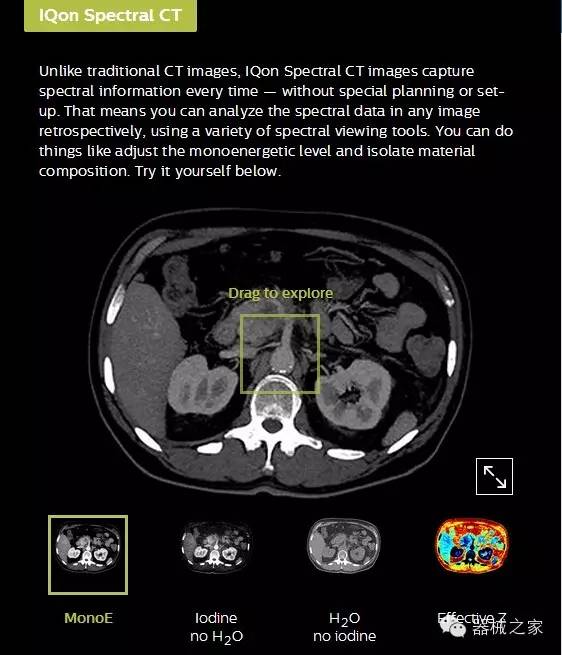

IQon光譜CT能夠按照需求提供光譜量化和工具,并能通過簡(jiǎn)單工作流程、在低劑量下對(duì)結(jié)構(gòu)進(jìn)行定性分析

IQon光譜CT -- 是業(yè)界首臺(tái)以探測(cè)器為成像基礎(chǔ)的光譜CT,它可以在單次常規(guī)掃描下獲得傳統(tǒng)解剖影像及光譜功能影像。不僅可以提供精準(zhǔn)的診斷信息,還可簡(jiǎn)化工作流程、在低劑量下完成定量與定性分析。